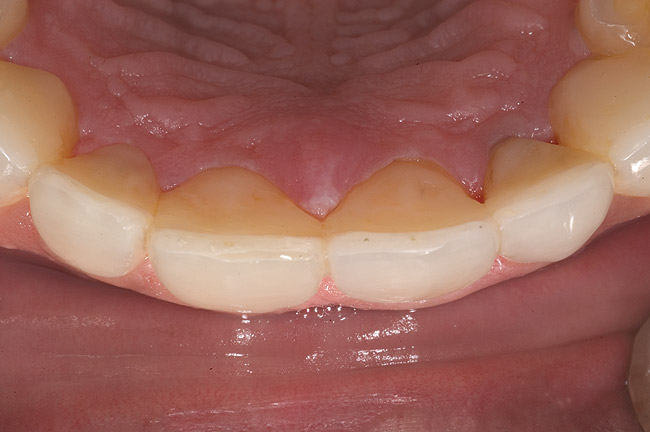

Figure 1 Normal overjet/overbite of anterior teeth

Figure 1

Acid dissolves the palatal enamel of upper anteriors, thus exposing the underlying dentin. This makes teeth appear higher in chroma and leads to hypersensitivity as well as supraeruption of opposing incisors. Clinically, this restricts the space needed to restore lost palatal tooth structure (Figure 1 and Figure 2).